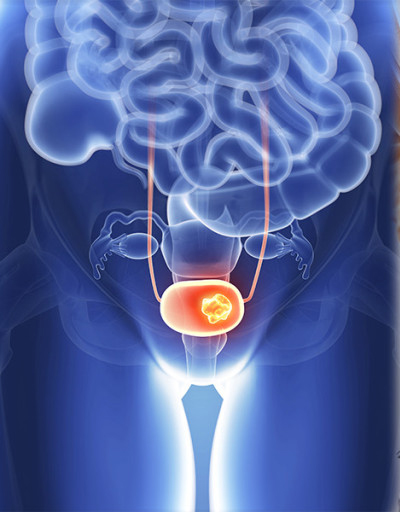

전립선암은 주로 전립선의 바깥쪽 부분인 말초대(Peripheral Zone)에서 발생합니다. 이 때문에 종양이 요도를 압박할 정도로 커지기 전까지는 증상이 나타나지 않는 경우가 많지만, 아래와 같은 비뇨기계 증상 및 전신 증상이 나타나기 시작하면 반드시 정밀 검사가 필요합니다.